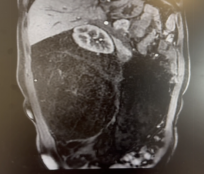

72岁男性,因体重下降2月,确诊腹膜后肉瘤10天。腹部增强CT提示左侧腹膜后巨大脂肪肉瘤,直径约30cm。

我们实施了全麻下开放腹膜后肿瘤切除术。术中发现肿瘤与结肠系膜及降结肠粘连,团队切除降结肠、部分膈肌、腹壁肌肉,横结肠和乙状结肠吻合。手术历时3个小时,出血控制在500ml以内。术后恢复良好:第2天下地活动,术后3天排气,术后1周流食,术后10天出院。